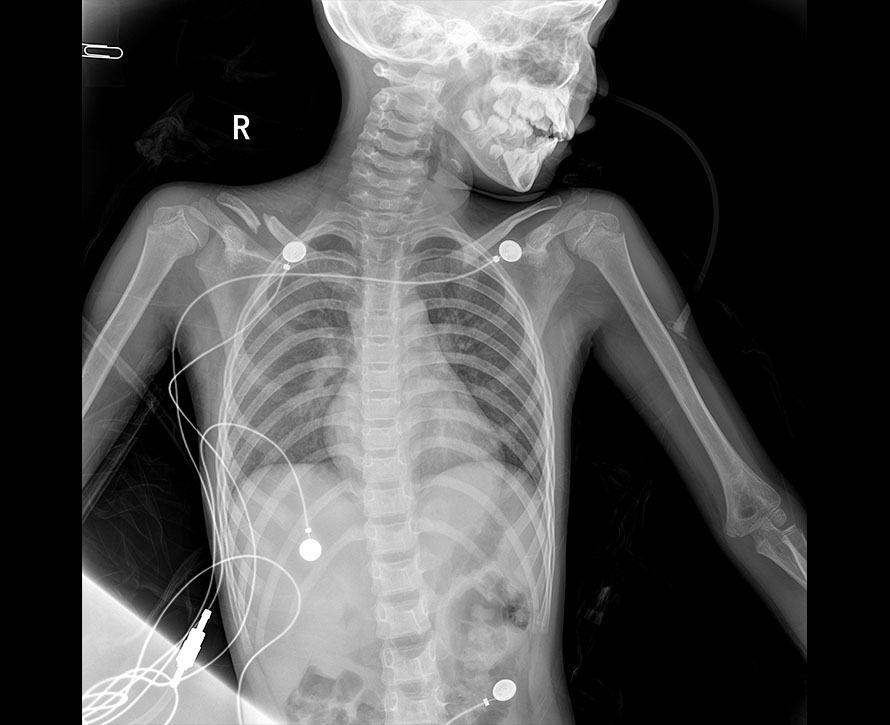

臨床圖像